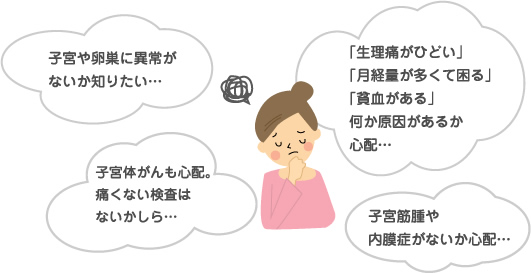

経腟超音波検査のおすすめ

通常の子宮頸がん検診は、細胞を取り調べる検査であり、子宮や卵巣の状態を画像でとらえていません。右記のようなお悩みがあり画像診断をご希望される方は、経腟超音波検査をおすすめします。

内診に続いて検査を行います。通常痛みはなく、1~2分程度で終わります。